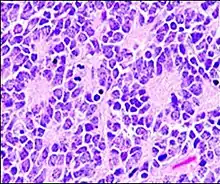

Structure of a Homer Wright pseudorosette

Perivascular pseudorosette

A perivascular pseudorosette consists of a spoke-wheel arrangement of cells with tapered cellular processes radiates around a wall of a centrally placed vessel. The modifier “pseudo” differentiates this pattern from the Homer Wright and Flexner-Wintersteiner rosettes, perhaps because the central structure is not actually formed by the tumor itself, but instead represents a native, non-neoplastic element. Also, some early investigators argued about the definition of a central lumen, choosing “pseudo” to indicate that the hub was not a true lumen but contained structures. Nevertheless, this pattern remains extremely diagnostically useful and the modifier unnecessarily leads to confusion. Perivascular pseudorosettes are encountered in most ependymomas regardless of grade or variant. As such, they are significantly more sensitive for the diagnosis of ependymomas than true ependymal rosettes. Unfortunately, perivascular pseudorosettes are also less specific in that they are also encountered in medulloblastomas, PNETs, central neurocytomas, and less often in glioblastomas, and a rare pediatric tumor, monomorphous pilomyxoid astrocytomas.[2]

Micrograph of perivascular pseudorosettes